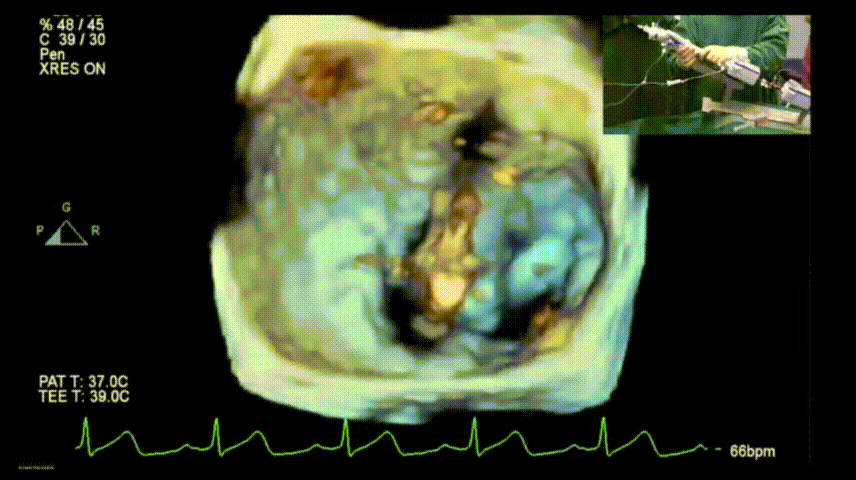

术前三维超声评估

图片